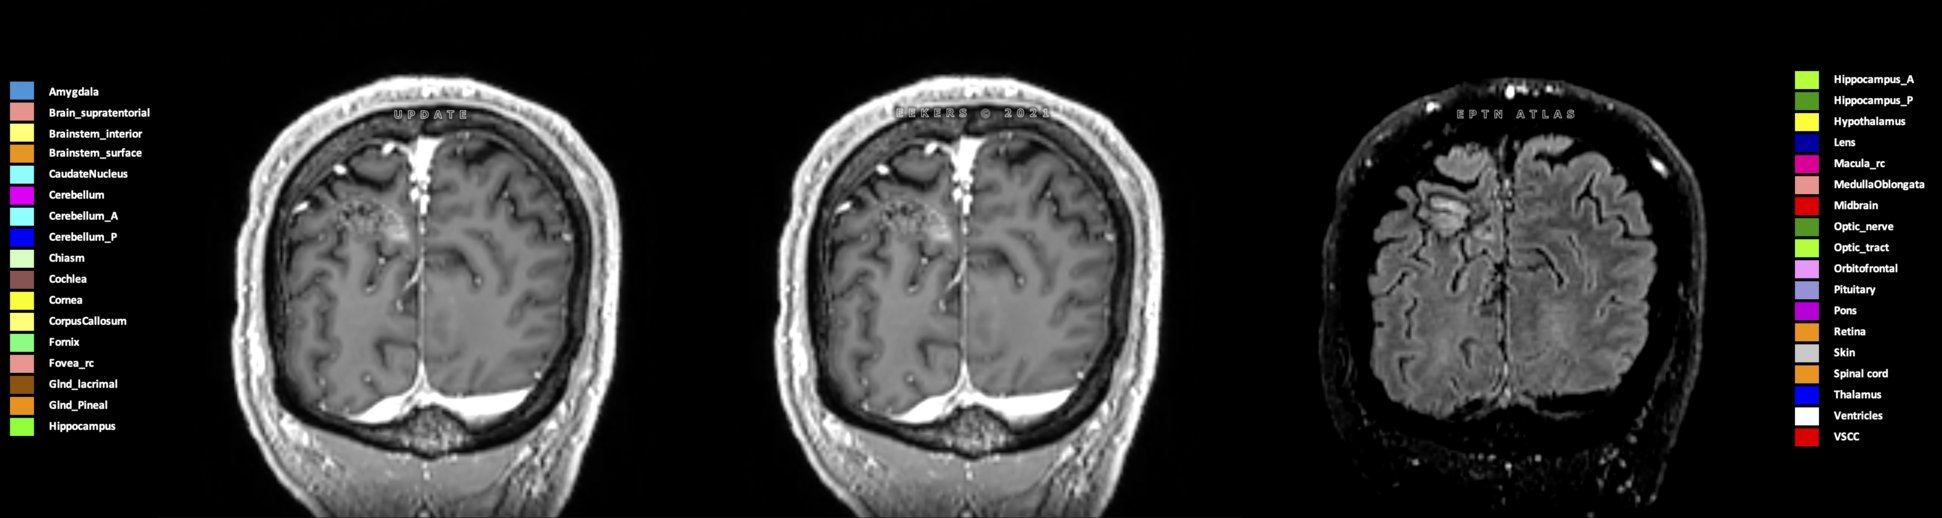

Eekers et al. have published an international neurological atlas for contouring of organs at risk in consensus with the European Particle Therapy Network (EPTN) in 2018 and an update in 2021. The purpose of this consensus atlas is to decrease inter- and intra-observer variability in delineating OARs relevant for neuro-oncology.

Included are all OARs known to be relevant for radiation-induced toxicity in neuro-oncology: brain, brainstem (midbrain, pons, medulla oblongata), chiasm, cerebellum (anterior & posterior), cochlea, cornea, hippocampus (anterior & posterior), hypothalamus, lens, lacrimal gland, optic nerve, pituitary, skin, and vestibular & semicircular canals. To further facilitate research on cognition, vision and radiological changes after irradiation of the brain, potential clinically-relevant OARs are included: amygdala, caudate nucleus, cerebellum (anterior & posterior), corpus callosum, fornix, macula, optic tract, orbitofrontal cortex, periventricular space (PVS), pineal gland, and thalamus.

Three-dimensional delineation of the 25 consensus OARs for neuro-oncology are shown on CT (WW/WL 120/40, 3000/600), 3T MR images, (T1Gd, T2FLAIR 1mm) and 7T MR (MP2RAGE 0.7 mm). All are presented in transversal, sagittal and coronal view.